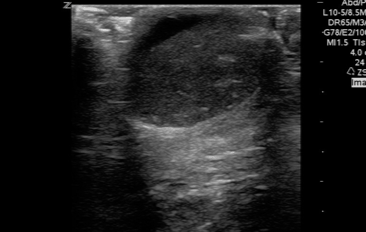

QA of the Day. Sudden Testicular pain, fluid around the teste. Turned out to be a ruptured epidermal inclusion cyst #pocus #foamus